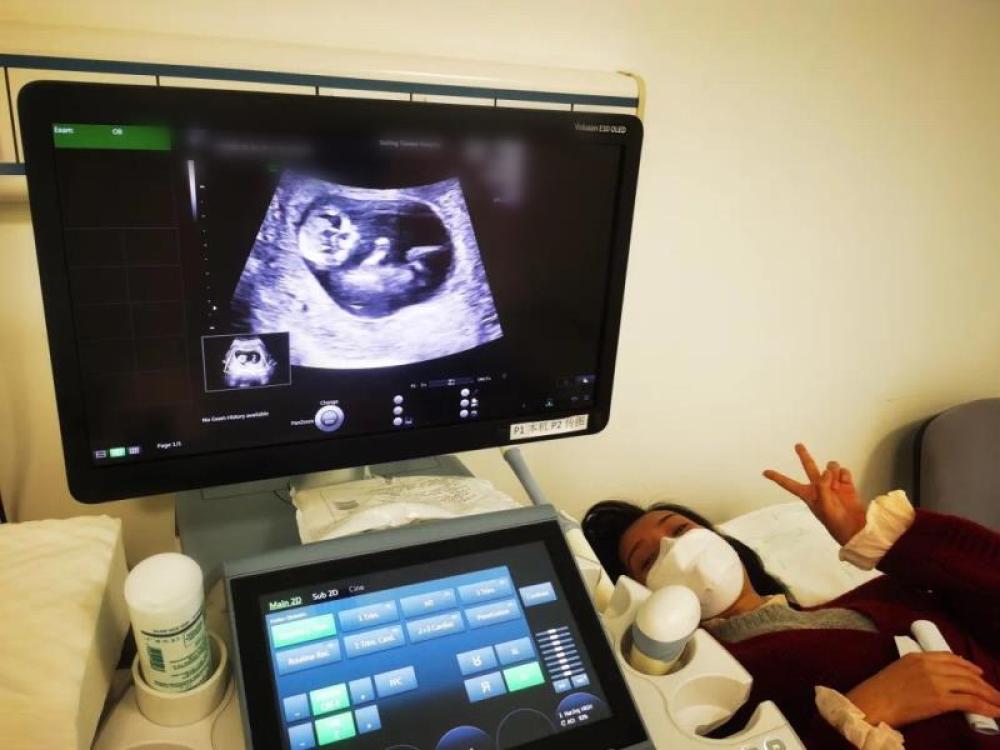

今天是我來武漢的第54天,第一次通過B超影像見到了“小家伙”。

今天一早,妻子去醫(yī)院進行B超檢查,同事用手機拍攝下了B超顯示屏上的畫面,記錄下了這個87天的小家伙第一次“亮相”。

圖為北京天壇醫(yī)院袁磊愛人做B超檢查。

“袁磊,看看你們家寶寶,可愛嗎?”收到同事發(fā)來的視頻,第一眼就看哭了,身邊的同事看完視頻也哭了。

視頻里,這個小家伙好像聽到了外面的召喚,在媽媽的肚子里伸手、踢腿、翻身,用各種動作進行回應(yīng)……看到他那小胳膊小腿,一種從未有過的幸福感不停地向上涌,眼淚怎么也控制不住。

其實在武漢這么多天,他一直就是我的牽掛,今天終于看到他了,那種感受真是又緊張又激動,雖然還看不清他的樣子,但是已經(jīng)感受到他的活力。